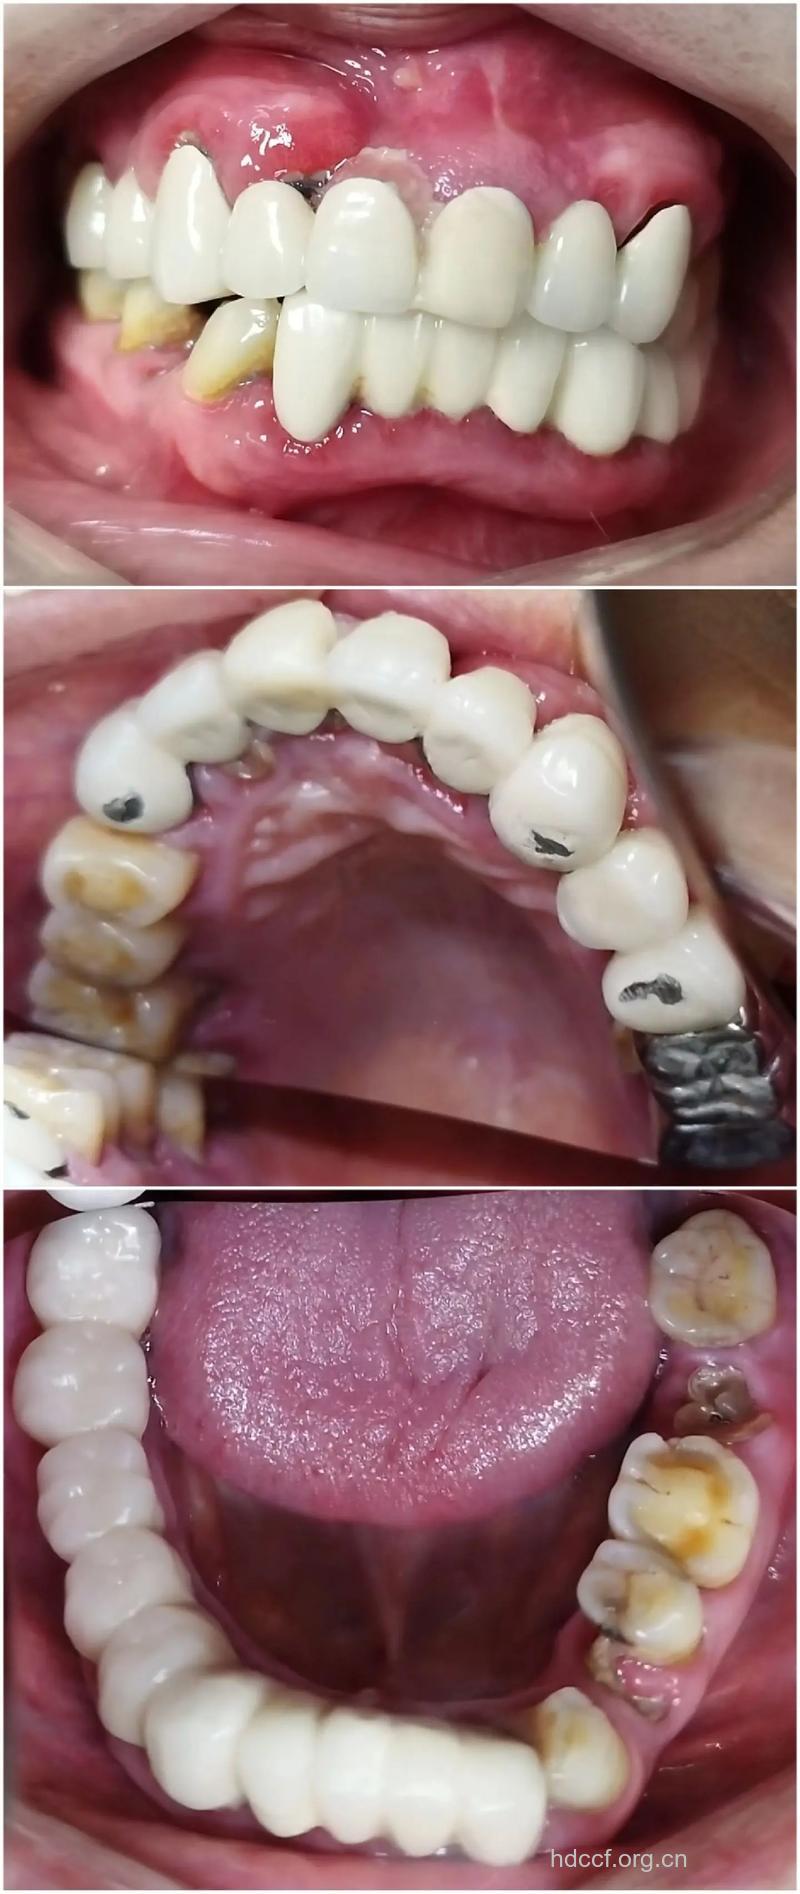

3、 崩瓷(烤瓷牙瓷质层和金属层分离,暴露出内层的金属颜色)

5、色泽欠佳

7、 牙龈着色

8、牙龈牙周病变(牙龈出血、牙齿松动等)